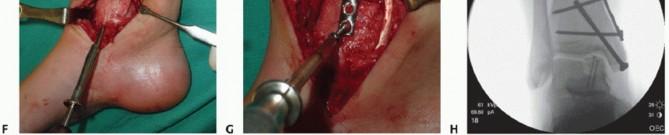

- TECH FIG 2 • A,B. Identifying the extent of the talar shoulder lesion. (continued)

- TECH FIG 2 • (continued) C-E. Excision of the talar shoulder lesion using the microsagittal and oscillating saws. F. Talar shoulder lesion removed.

- TECH FIG 3 • A. The dimensions of the recipient site are carefully recorded and transferred to the allograft. B. Two pointed reduction clamps are used to stabilize the allograft during preparation. C. Donor allograft with newly prepared graft removed.

- TECH FIG 4 • A-C. Fitting and securing the graft to the native talus. A. After contouring the graft (some minor discoloration from debris while manipulating graft on back table; it is easily washed away). B. Drill hole perpendicular to graft. C. Securing graft with two countersunk screws. (continued)

- TECH FIG 4 • (continued) D,E. A different patient with similar graft, excellent interference fit, and secured with a single screw. D. Screw is inserted in lag fashion. E. Screw head is countersunk. F-H. Reduction of the medial malleolar osteotomy. F. Screw fixation through the predrilled holes. G. Antiglide plate. H. Final fluoroscopic evaluation of graft and reduction of medial malleolar osteotomy. Despite optimal clinical fit of the graft, rarely does the fluoroscopic appearance suggest anatomic graft match to the native talus, typically due to differing cartilage thicknesses between the donor and the host. Although the screws may appear prominent, two-dimensional fluoroscopy is deceiving because the screws are countersunk below the articular surface of the graft and the talar dome is curved.